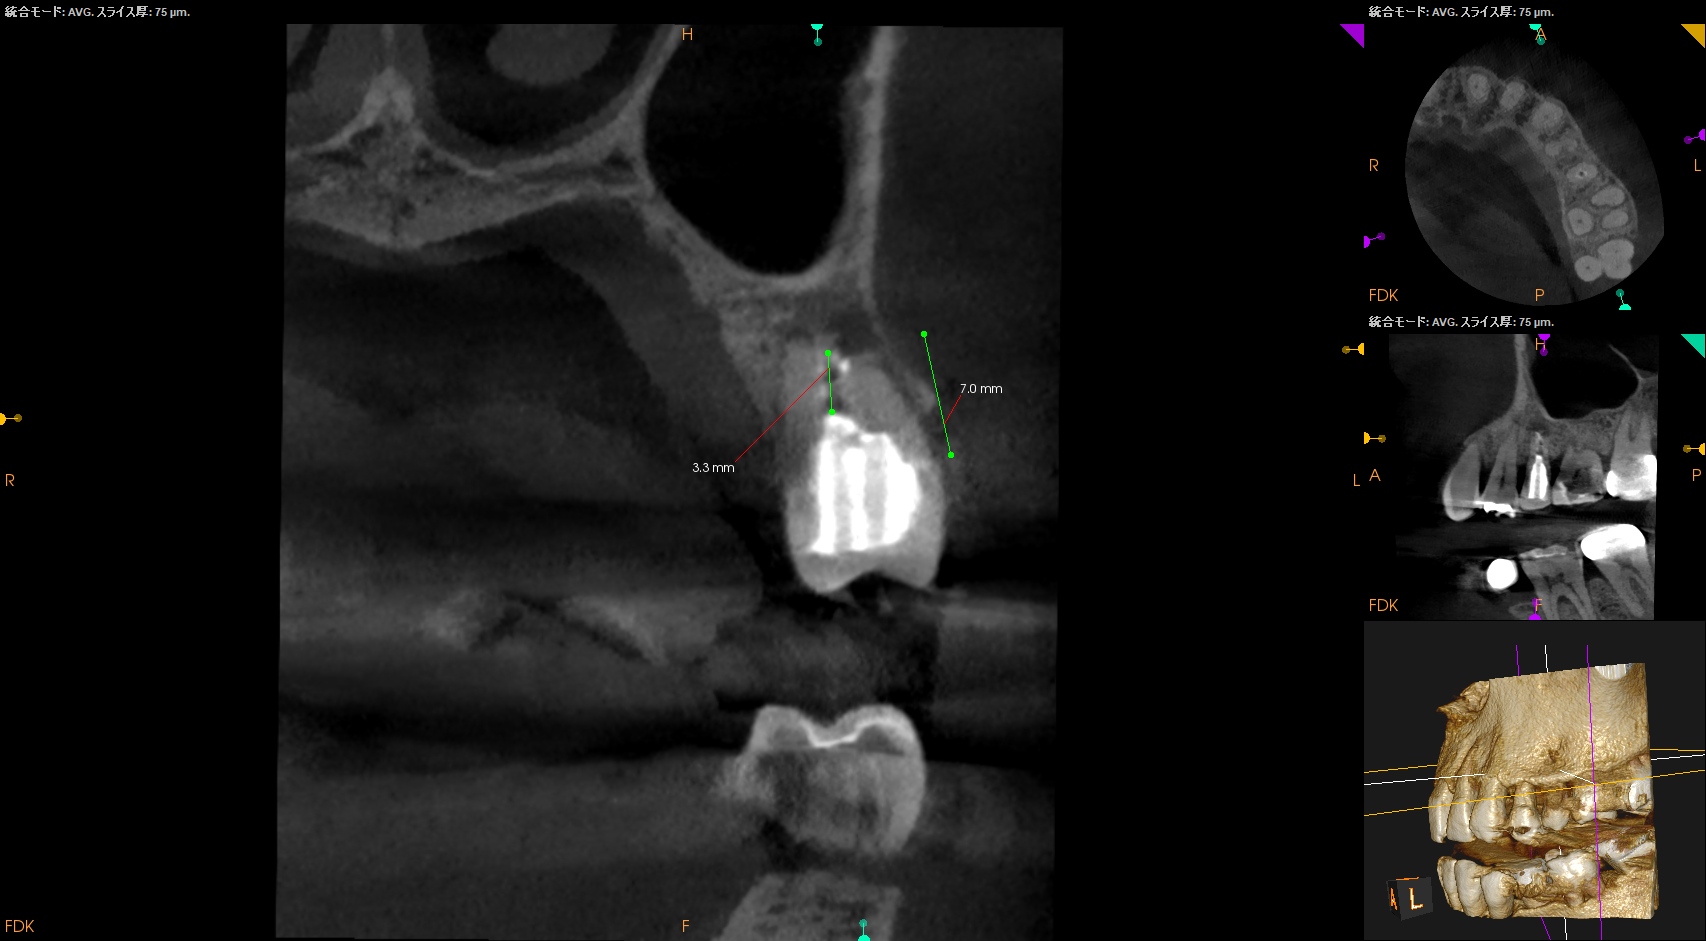

術後にPA, CBCTを撮影した。

再度、何らかの原因で逆根管充填材が外れないように深く逆根管充填した。

今回の修正は、

逆根充材の厚みを増してみるというその1点のみである。

やはり浅い逆根管充填はそれが外れやすいというリスクがあるようだ、と私はこのケースから感じた。